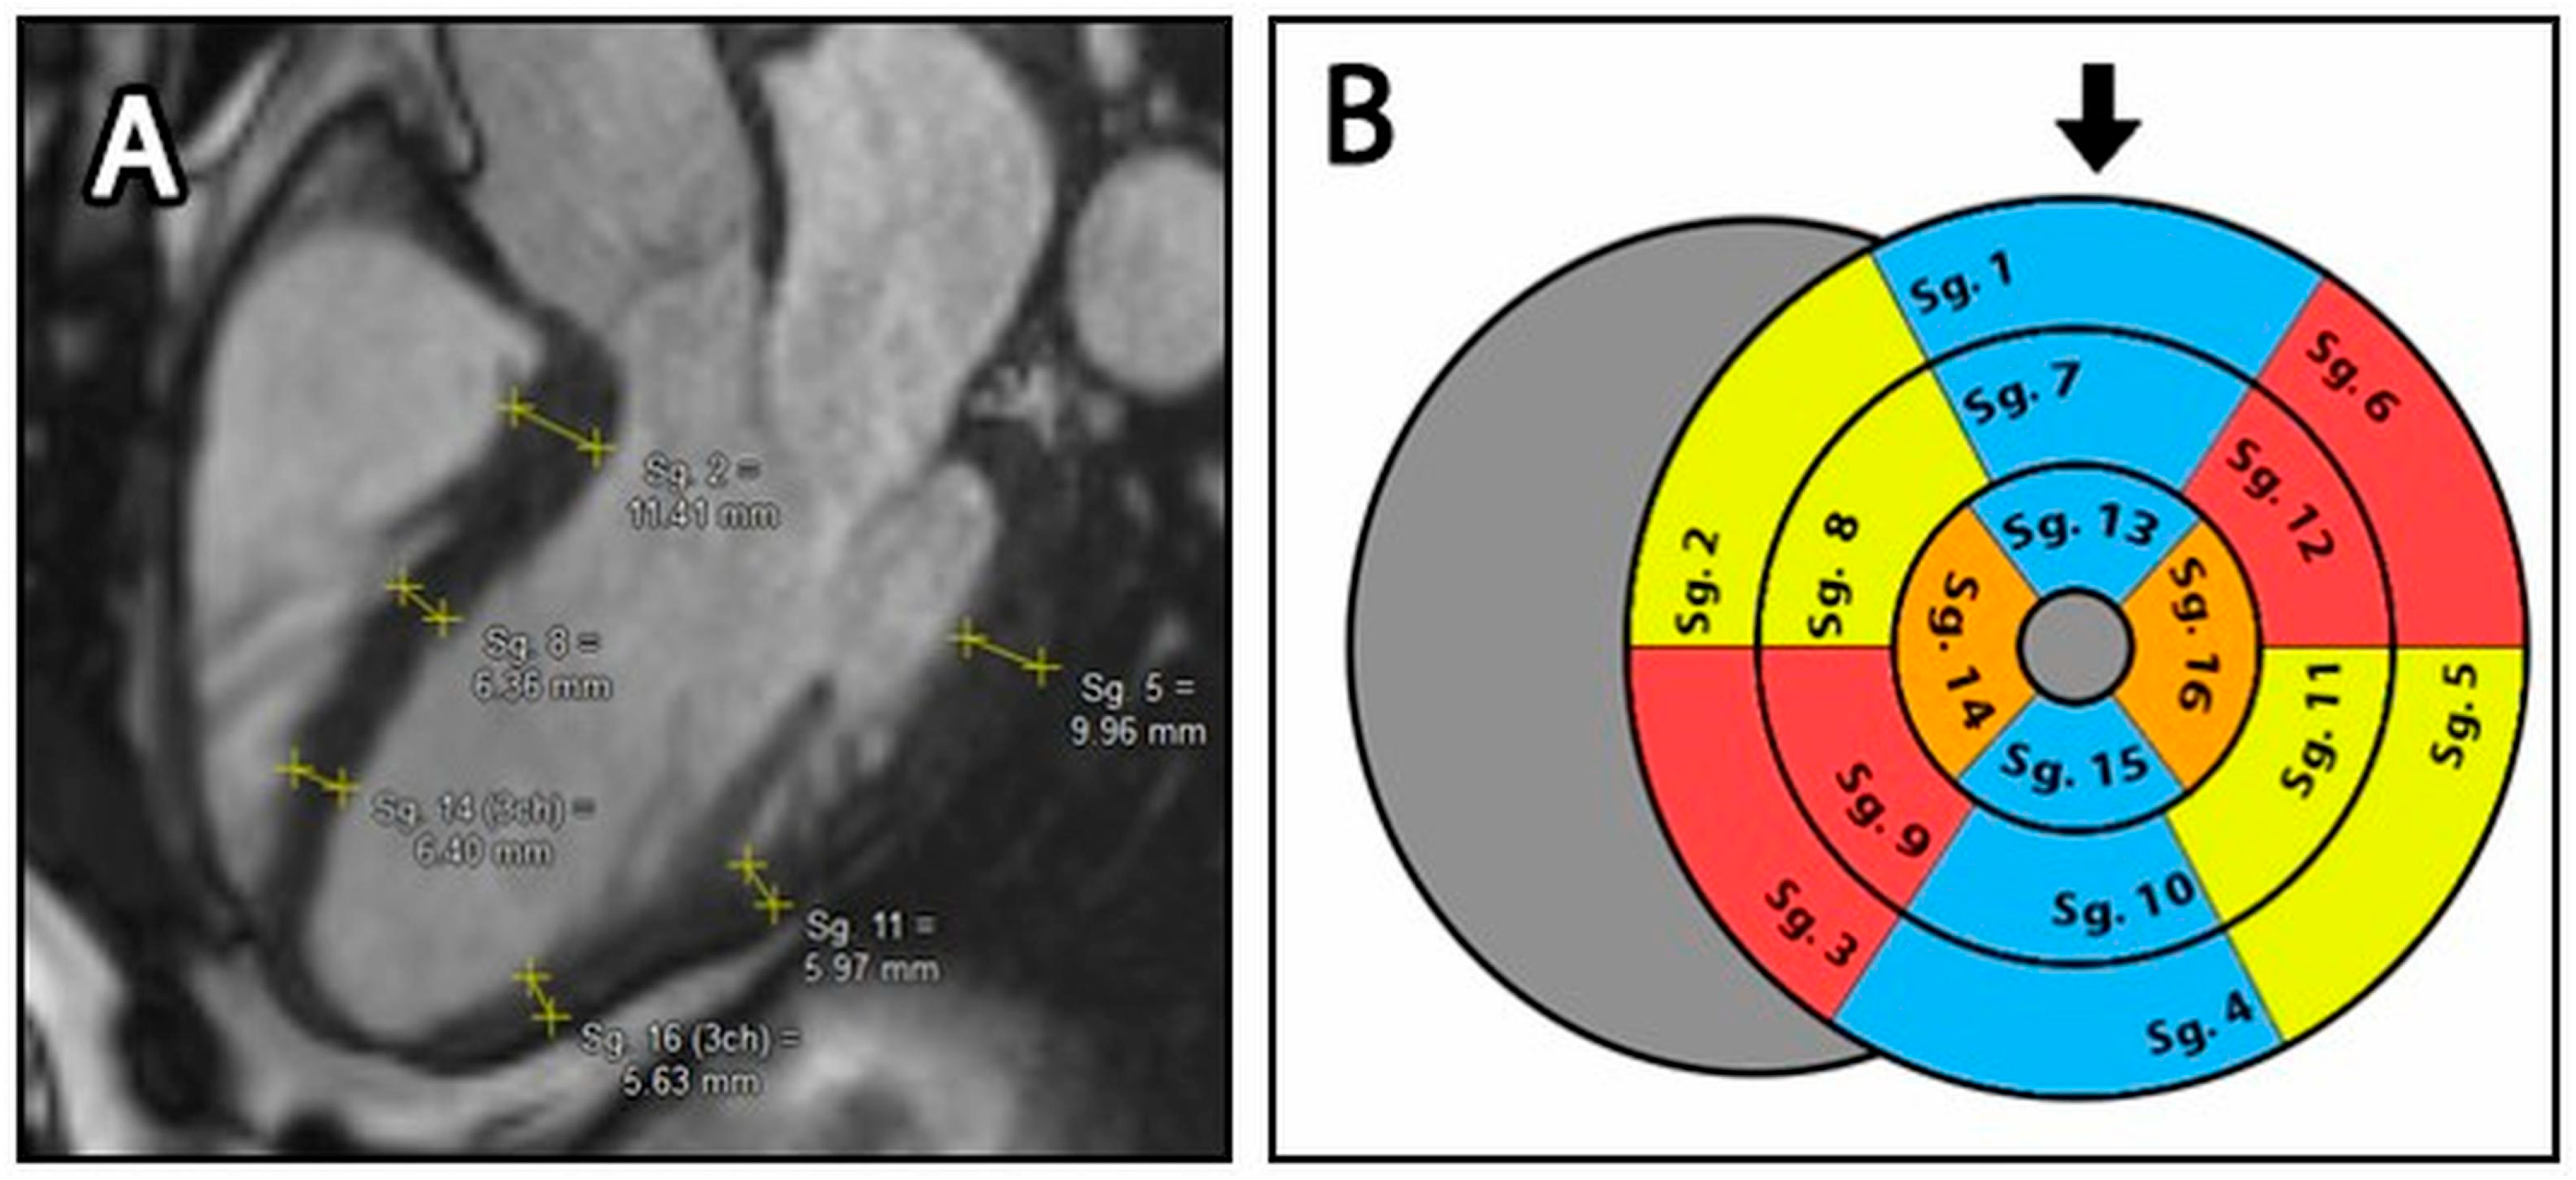

For the manual compact layer thickness analysis, long axis images (LAX) in 2-, 3- and 4-chamber views were used. According to current guidelines, wall thickness measurement was based on the American Heart Association (AHA) 17-segment left ventricular model, where thickness of the compact layer was measured in all segments except segment 17, the cardiac apex [23,24]. In this modified 16-segment model, within each segment, one wall thickness measurement was performed using the Medis Suite distance measuring tool (accuracy 2 tenths of a mm). The location of the segment margins and the position of the measured point within segments were determined subjectively by the readers, who were trying to find the average wall thickness of each segment (Figure 2A) [9].

Figure 2.

(A): Manual distance measurement on the LAX 3 chamber image. Yellow lines represent individually measured wall thickness of each segment. (B): Bullseye plot of the LV with the modified 16-segment model. The blue segments represent the 2-cavity plane, the yellow segments represent the 3-cavity plane and the red segments represent the 4-cavity plane. The orange areas indicate regions that belong to both the 3- and 4-cavity areas. Sg.: Segments, the black arrow represents the anterior wall.

The thickness of the septal and lateral walls in the apical third (Seg. 14 & 16) was obtained by averaging the apical third of the 3- and 4-chamber views.

For a detailed evaluation, we calculated not only the thickness values of each segment, but also the average thickness of the basal (Seg. 1–6), mid (Seg. 7–12) and apical (Seg. 13–16) segments (Figure 2B).